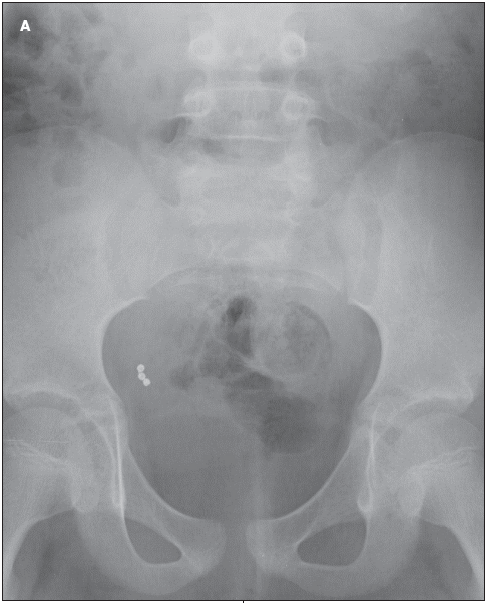

The patient is an 8-year-old girl with a history of asthma and developmental delay. She complained of hip pain, and her pediatrician referred her to a pediatric orthopedist for consultation. Hip x-ray films were ordered; they revealed 3 round beads in the child's appendix (A). The child's mother remembered that the child had been chewing on a beaded bracelet 1 to 2 months before the films were taken.

The child's hip pain subsequently resolved and the results of an abdominal examination were normal, according to John Harrington, MD, Michael Morris, MD,

and Whitney McBride, MD, at the Maria Fareri Children's Hospital at New York Medical College in Valhalla, NY. Nevertheless, the child underwent elective appendectomy to remove the beads (B). She recovered uneventfully.